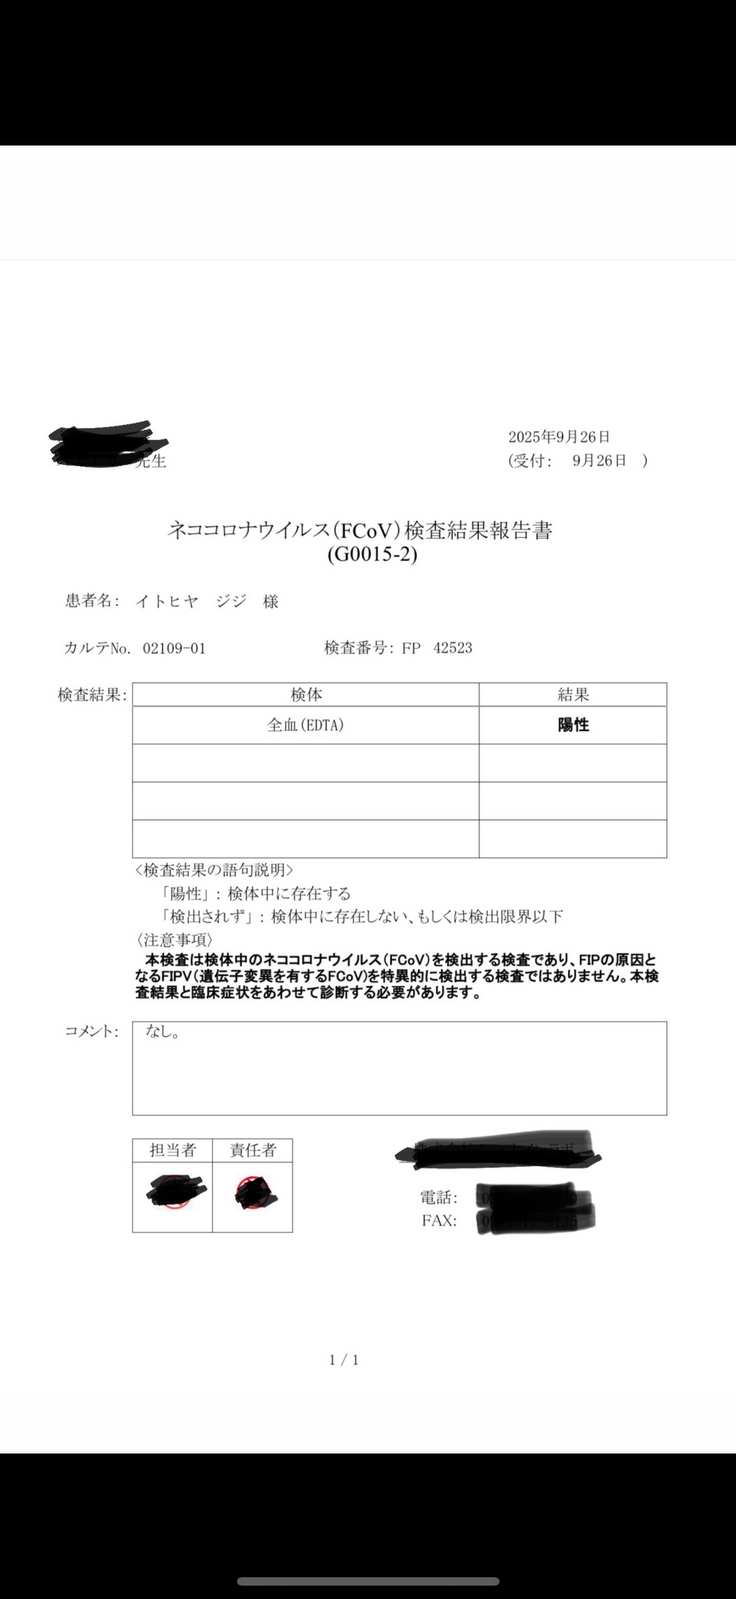

この日に初めて猫伝染性腹膜炎(FIP)かもしれないという話をされました。

そして詳細の検査の結果、9/26、正式にFIP(Wetタイプ)と診断を受けました。

私はジジがFIPかもしれない、と言われて初めてこの病気を知りました。